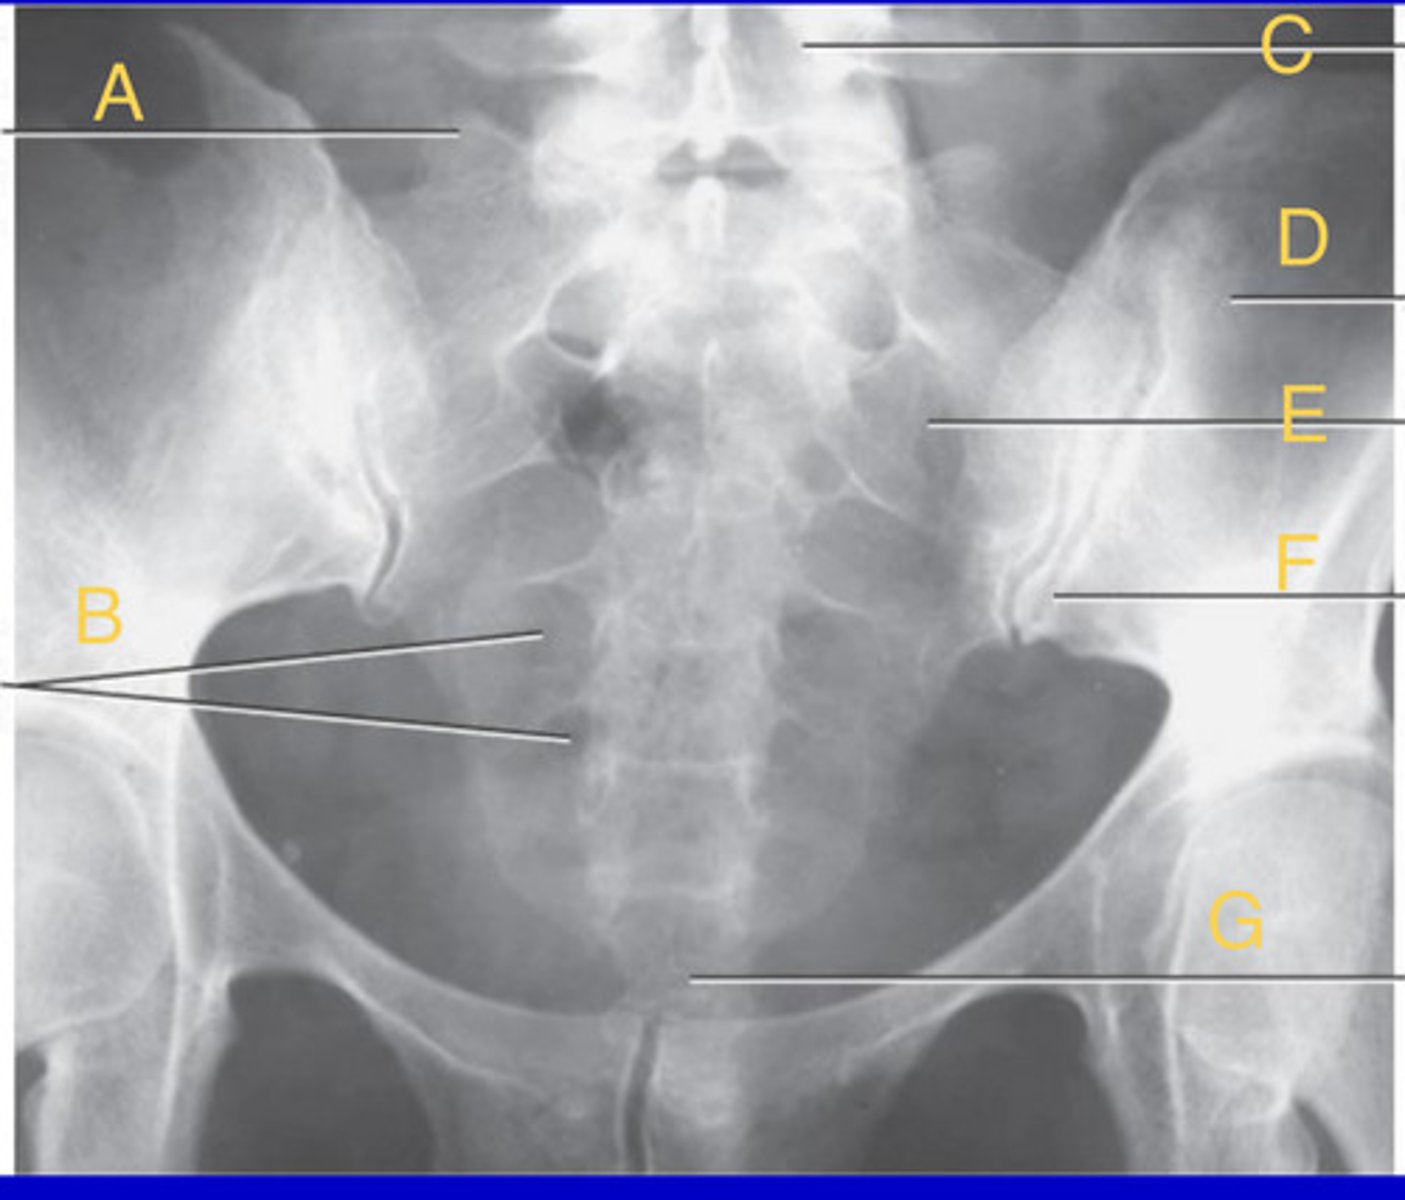

L2 Pedicle

A.

L2-3 intervertebral foramina

B.

L3-4 intervertebral joint space

C.

L4 body

D.

L5-S1 articular process

E.

Sacrum

F.

Greater sciatic notch

G.

L5-S1 joint

H.

Lateral Lumbar

What position?